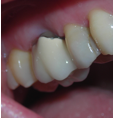

Conventional Treatment with Standard Core Restoration

Non-surgical endodontic treatment with resin core build up